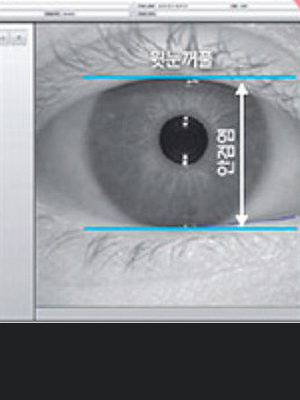

• 각막곡률

(모양)검사

• 각막크기 및

동공크기 검사

• 눈의 크기 및

눈꺼풀상태 검사